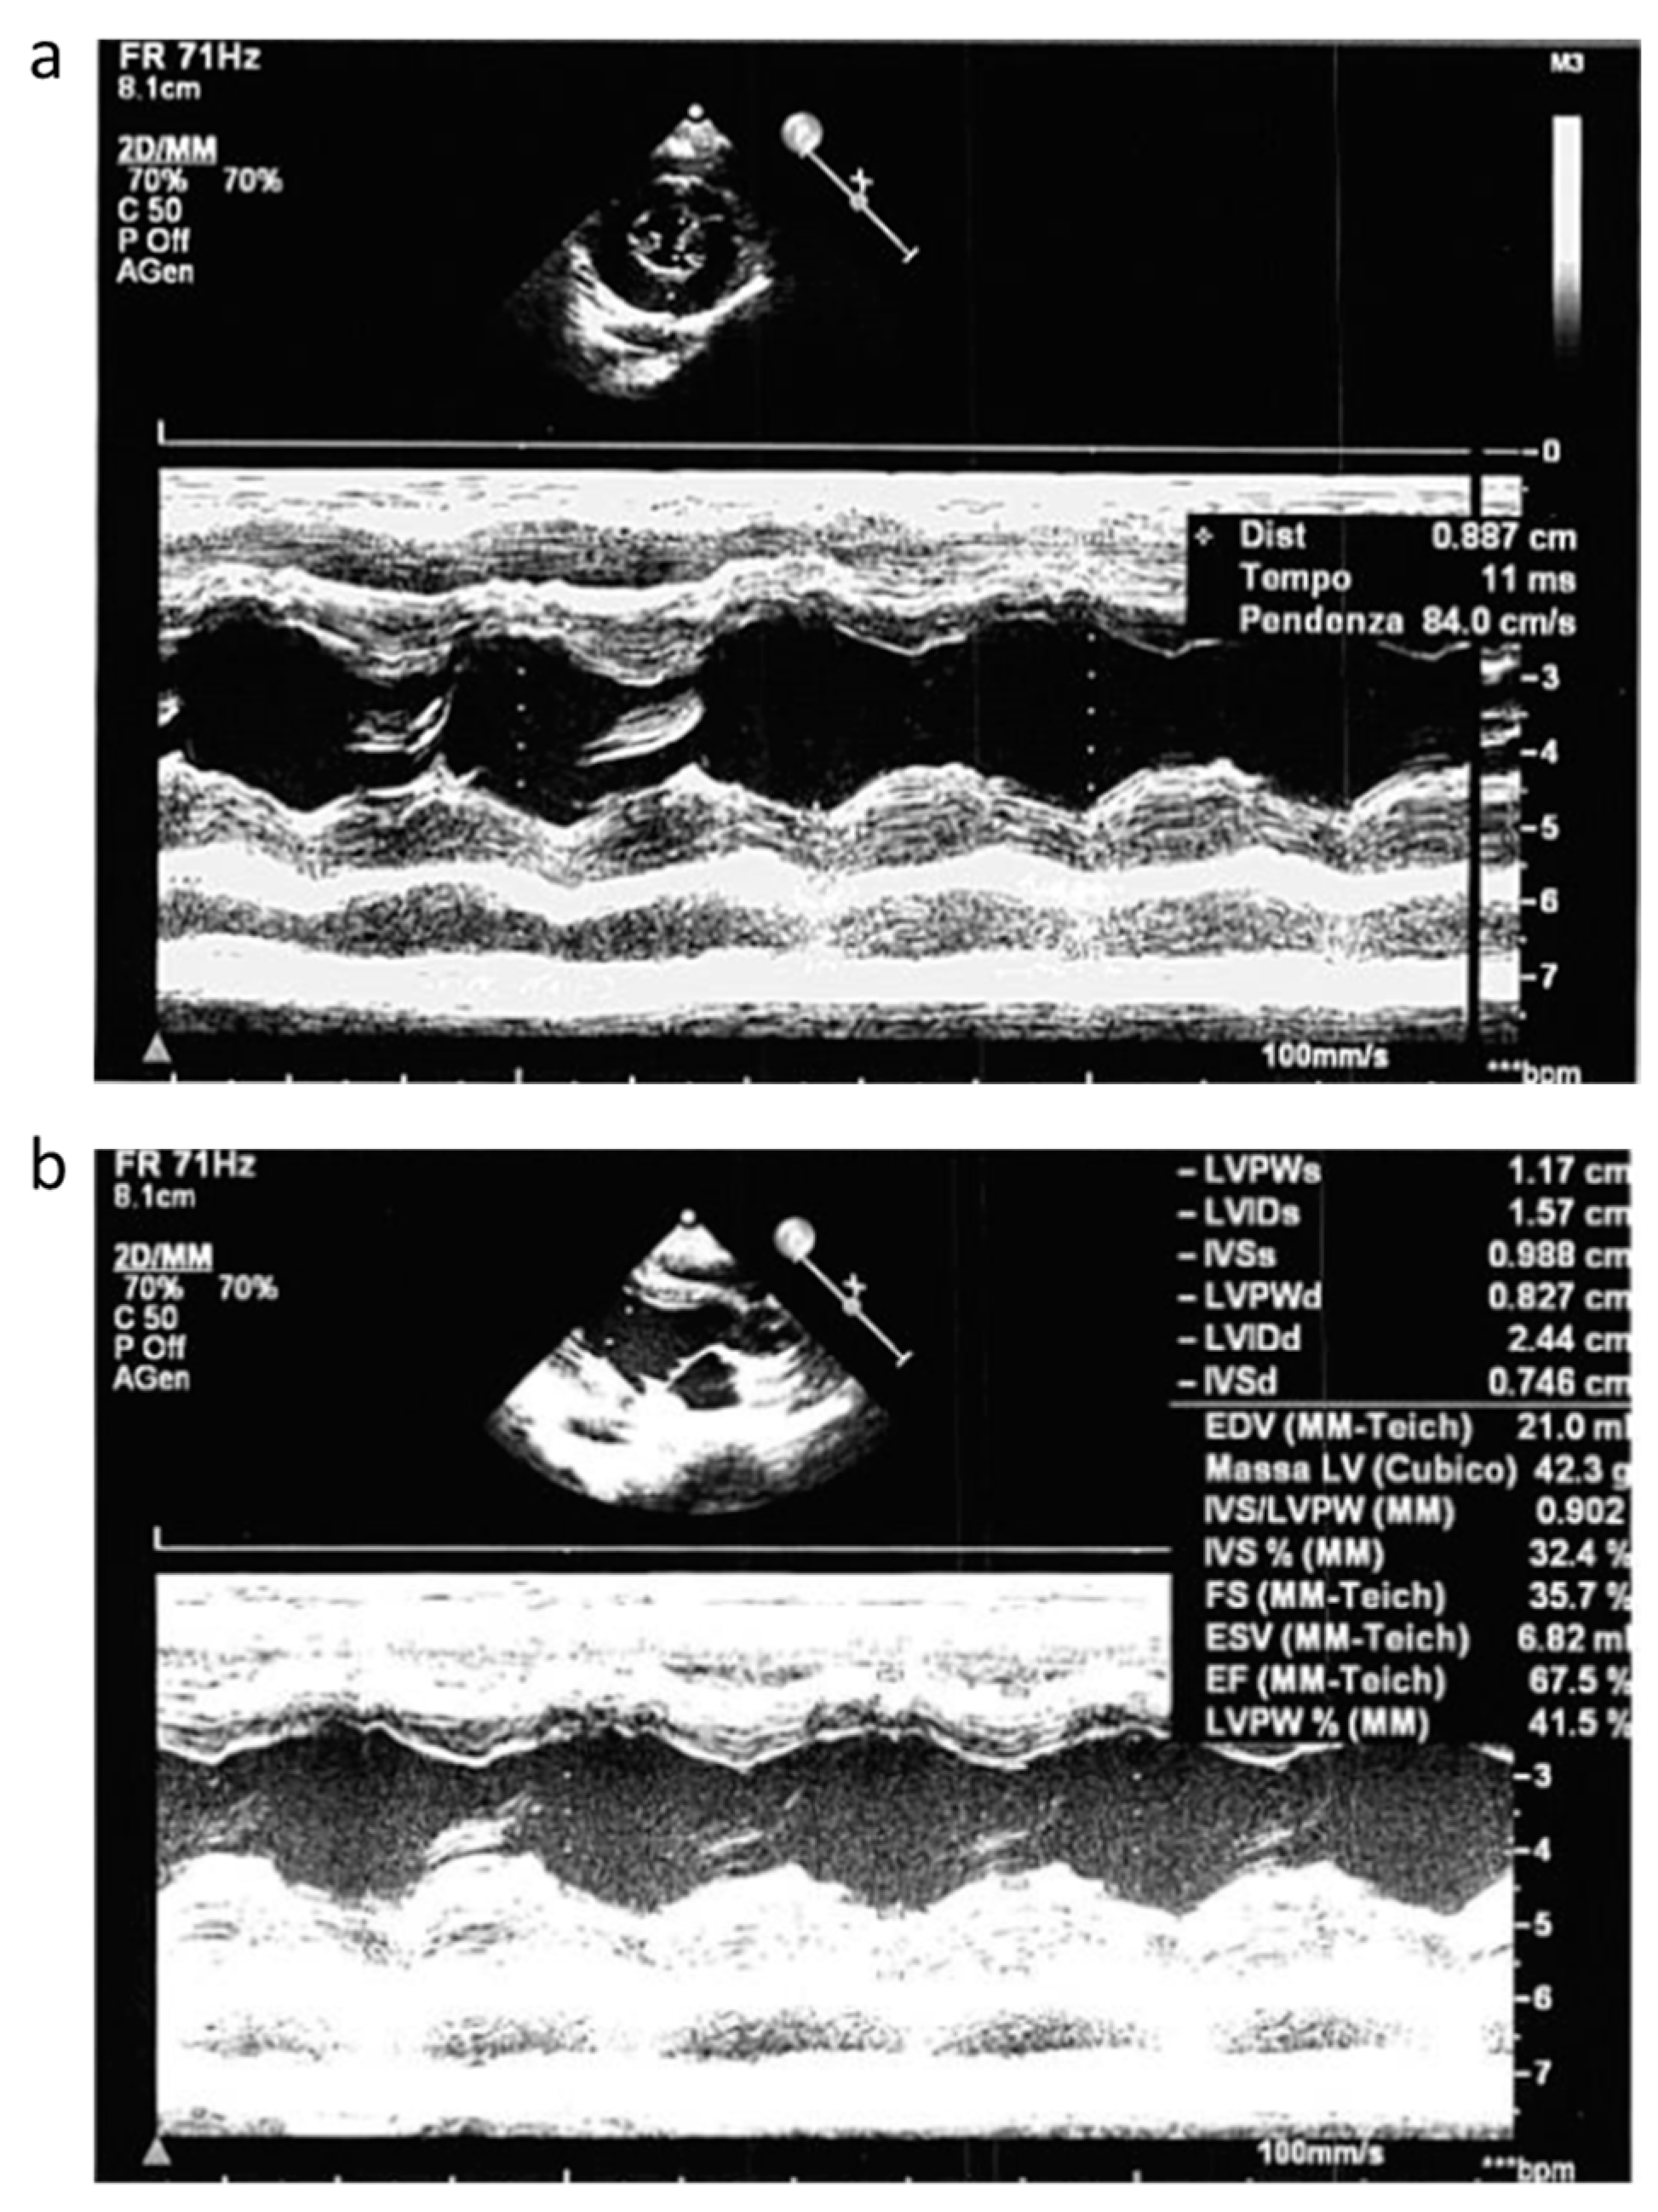

Concomitant cardiac evaluation with echocardiogram showed a moderate hypertrophic cardiomyopathy of the left ventricle (Figure 2a) without outflow obstruction and with normal ejection fraction (EF) (Figure 2b).

Figure 2. Echocardiogram pattern. Echocardiogram performed during acute phase that showed moderate hypertrofic cardiomyopathy of the left ventricle (a) without outflow obstruction and with normal EF (b).